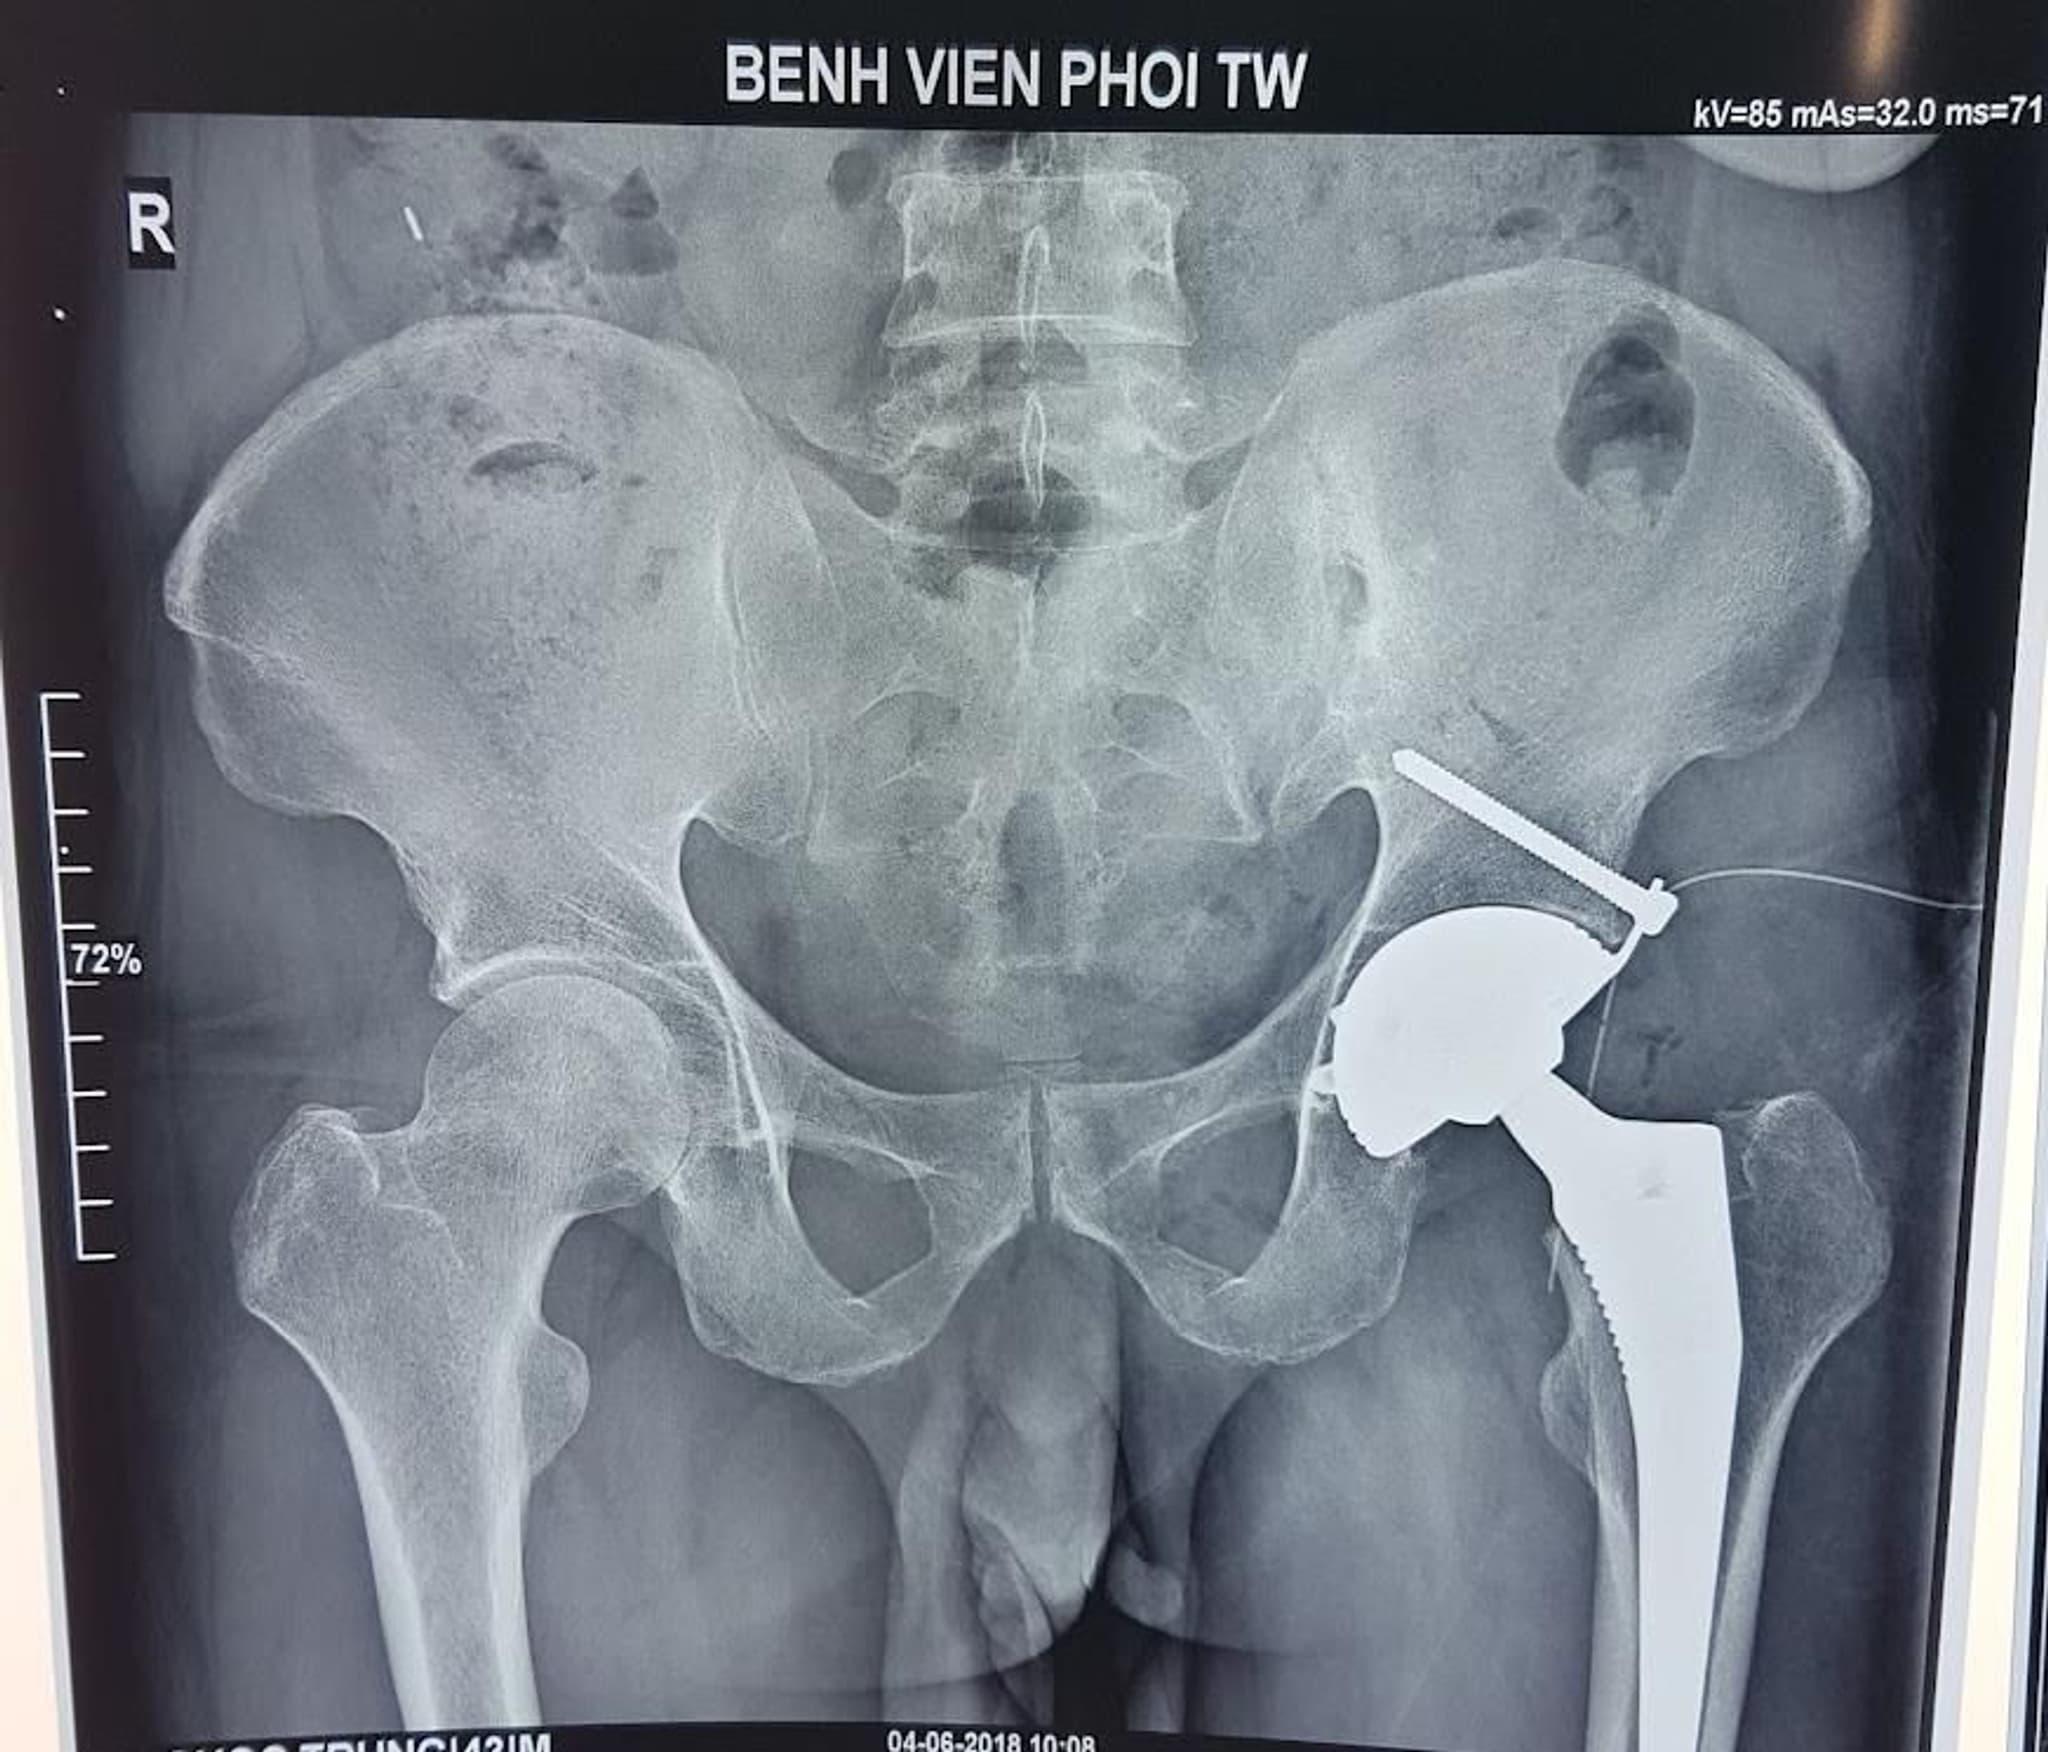

THAY KHỚP HÁNG NHÂN TẠO – BƯỚC ĐỘT PHÁ GIÚP NGƯỜI BỆNH LAO KHỚP HÁNG TÁI HÒA NHẬP CUỘC SỐNG BÌNH THƯỜNG

THAY KHỚP HÁNG NHÂN TẠO - BƯỚC ĐỘT PHÁ GIÚP NGƯỜI BỆNH LAO KHỚP HÁNG TÁI HÒA NHẬP CUỘC SỐNG BÌNH THƯỜNG Lao khớp háng cho đến nay vẫn còn là bệnh lý khó chẩn đoán và điều trị. Bệnh...